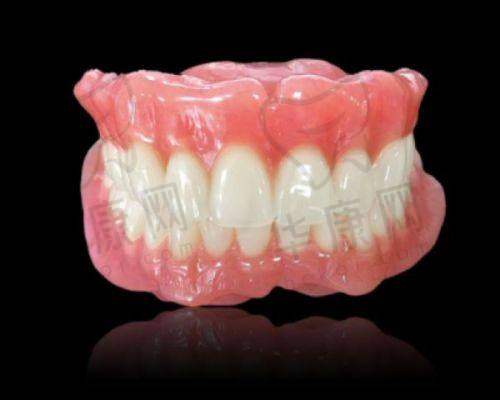

在激烈的市场竞争下,2024年西安各口腔医院收费标准有一定下调。种植牙方面,价格基本在2980 - 8800元起一颗。其中,国产种植牙价格在2680 - 3980元起一颗(创英、威高);韩国进口种植牙价格在2980 - 4980元起一颗(登腾、奥齿泰、美格真、仕诺康);美国进口种植牙价格在4980 - 6980元起一颗(皓圣、杰美);德国进口种植牙价格在5980元起一颗(icx、朗斯、camlog、贝格);瑞士进口种植牙价格在6980 - 10800元起一颗(iti、sic);瑞典进口种植牙在7980 - 10800元起一颗(诺贝尔、astra)。